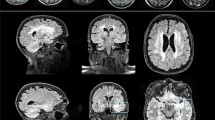

White matter hyperintensities (WMH) are typically segmented using MRI because WMH are hardly visible on 18F-FDG PET/CT. This retrospective study was conducted to segment WMH and estimate their volumes from 18F-FDG PET with a generative adversarial network (WhyperGAN).

We selected patients whose interval between MRI and FDG PET/CT scans was within 3 months, from January 2017 to December 2018, and classified them into mild, moderate, and severe groups by following the semiquantitative rating method of Fazekas. For each group, 50 patients were selected, and of them, we randomly selected 35 patients for training and 15 for testing. WMH were automatically segmented from FLAIR MRI with manual adjustment. Patches of WMH were extracted from 18F-FDG PET and segmented MRI. WhyperGAN was compared with H-DenseUnet, a deep learning method widely used for segmentation tasks, for segmentation performance based on the dice similarity coefficient (DSC), recall, and average volume differences (AVD). For volume estimation, the predicted WMH volumes from PET were compared with ground truth volumes.

Although limited by visual analysis, the WhyperGAN based can be used to automatically segment and estimate volumes of WMH from 18F-FDG PET/CT. This would increase the usefulness of 18F-FDG PET/CT for the evaluation of WMH in patients with cognitive impairment.